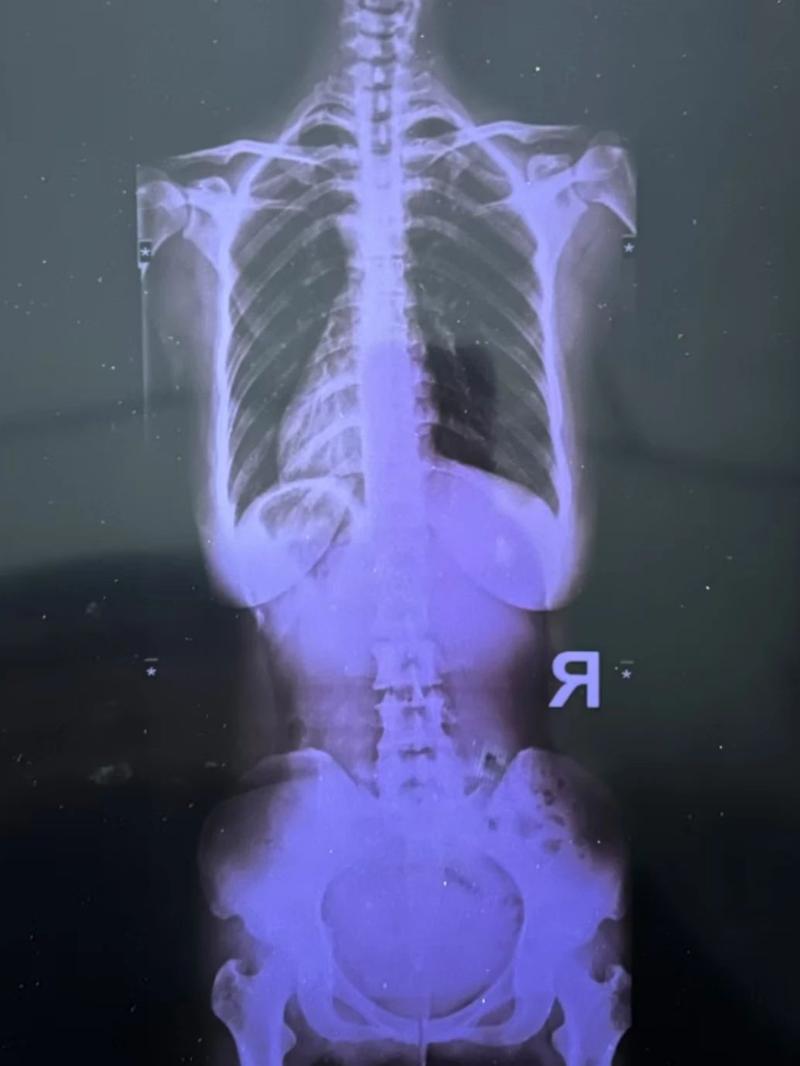

最(zui)近又疼起來嚴重影響正常生活,她前往醫院就診,結果(guo)查出了脊柱側彎11°,骨盆旋移,骶髂(qia)關(guan)節半脫位,由于這些導致(zhi)頸肩,后(hou)背,腰(yao)部(bu)肌群代償出現(xian)問題,從而出現(xian)腰(yao)痛(tong),后(hou)背痛(tong),肩膀痛(tong)!